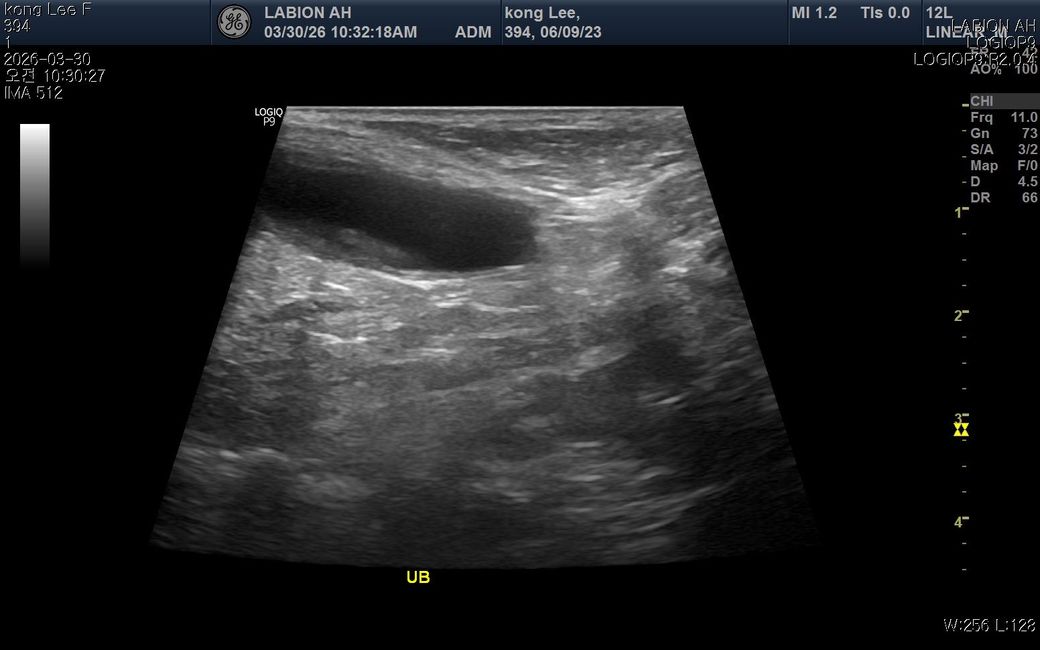

최근 황태 간식을 약 2~3개월 동안 매일 급여해왔고 염분이 느껴져 급여를 중단했습 니다. 이후 소변횟수가 살짝 감소하고 음수량이 평소보다 증가했고 동시에 밤잠이 줄고 낮에 무기력해졌습니다 원래 저녁에8시간정도 잤는데 중간에 한두번씩 깨거나 6시간으로 줄었고 밤잠이 줄어 낮에 좀 피곤해하는데 혹시 나트륨 섭취로 인해 체내 호르몬에 이상이 생긴걸까요? 2년전 슬개골 수술이력도 있지만 시기가 너무 겹쳐서 궁굼합니다

• 과도한 나트륨 섭취는 체내 전해질 불균형을 유발하여 음수량 증가와 배뇨 패턴 변화를 일으킬 수 있으며 이는 수면의 질을 저하시키는 직접적인 원인이 됩니다. 염분이 많은 간식을 장기간 섭취하면 신장에 부담을 주어 일시적인 대사 이상이나 다갈 및 다뇨 증상이 나타날 수 있고 이로 인해 야간에 갈증을 느끼거나 배변 욕구가 생겨 잠에서 자주 깨게 됩니다. 수면 부족이 낮 시간의 무기력증으로 이어지는 것은 자연스러운 현상이지만 증상이 지속된다면 단순히 식이 문제가 아니라 부신피질 기능 항진증과 같은 호르몬 질환 가능성을 배제할 수 없으므로 혈액 검사를 통한 수치 확인이 필요합니다. 슬개골 수술 이력과 직접적인 연관성은 낮아 보이나 통증으로 인한 불면일 수도 있으니 식단 조절 후에도 음수량이 줄지 않는다면 즉시 정밀 진단을 받는 것이 합리적입니다.